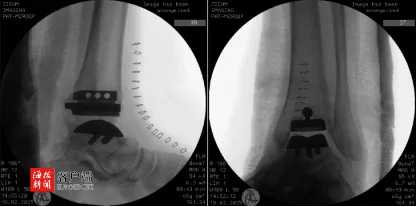

以往患者只要一听到需进行此类高难度手术,大多会选择前往北上广深等省外大医院就诊,但陈先生作为贾主任的“老病号”,对海南医科大学第一附属医院关节外科贾主任团队充满信心,他请求由贾主任主刀开展手术。经过周密的术前准备,贾主任团队利用数字疗法试验中心的技术优势,精心设计并定制了个性化的3D截骨导板,模拟截骨,以确保假体植入的精准匹配。在手术团队的不懈努力之下,踝关节假体位置放置精准,手术圆满成功。术后,陈先生生命体征平稳。手术次日,陈先生左踝关节疼痛已较术前得到明显缓解。